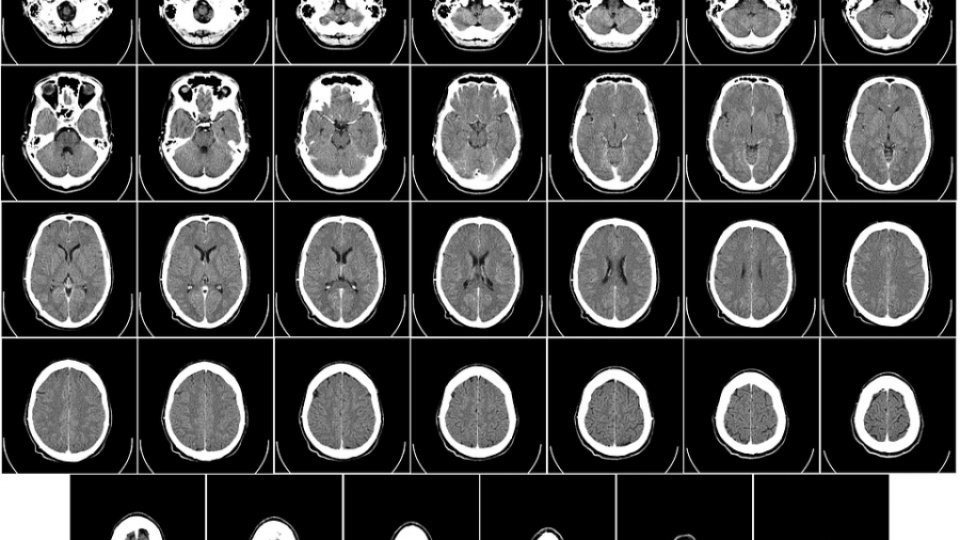

Meningita este o inflamație a meningelor

Indiferent dacă este de origine bacteriană sau virală, meningita corespunde – după cum sugerează și numele – unei infecții a membranelor din jurul creierului și în special a măduvei spinării. Cazurile de meningită bacteriană sunt cele mai puțin frecvente, dar cele mai grave. Ele apar cel mai adesea la copii. Fără tratament urgent, meningita bacteriană este o afecțiune care poate duce rapid la prognosticul vital al pacientului, o comă sau chiar abcese cerebrale. Prin urmare, îngrijirea trebuie făcută în regim de urgență extremă. Cu toate acestea, severitatea acestei afecțiuni va depinde de natura agentului patogen cauzal. De aceea este esențial să cunoaștem simptomele pentru a le putea identifica rapid. Meningita virală este mult mai frecventă și de obicei benignă. Se referă în general la o populație formată din adulți tineri.